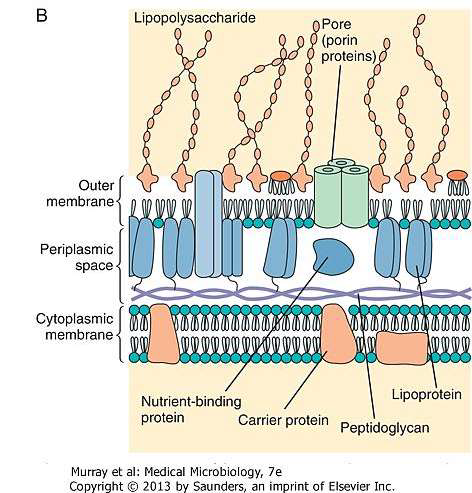

- Lipopolysaccharide (LPS)

- Lipid A 致病

- Core 含2-keto-3-

deoxy-octanoate(KDO)

格蘭氏染色

Negative

- 雙層膜

- Lipopolysaccharide (LPS)

- Peptidoglycan

Endotoxin

A.K.A Lipopolysaccharide (LPS)

- 可活化血小板及凝血系統為革蘭氏陰性菌造成敗血症的主因